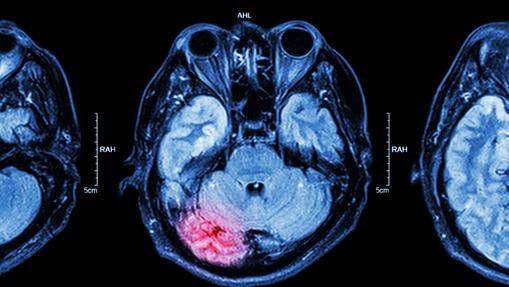

En concreto, los epilépticos a veces tienen sensaciones que describen como «elevación del suelo», «alejamiento de uno mismo» o «salir fuera del cuerpo». Por suerte, los neurólogos han vinculado estas inquietantes vivencias con una actividad anómala del lóbulo temporal del hemisferio derecho. Una actividad que, por cierto, aparece justo antes de los ataques epilépticos.

Si todavía así le queda un resquicio de duda, el neurocirujano canadiense Wilder Penfield dio con una forma de inducir la sensación de levitación. En operaciones quirúrgicas para tratar ciertos tipos de epilepsia, comprobó que estimulando con electricidad un área concreta, los pacientes decían verse flotando en el aire y contemplando su propio cuerpo en la mesa de operaciones.